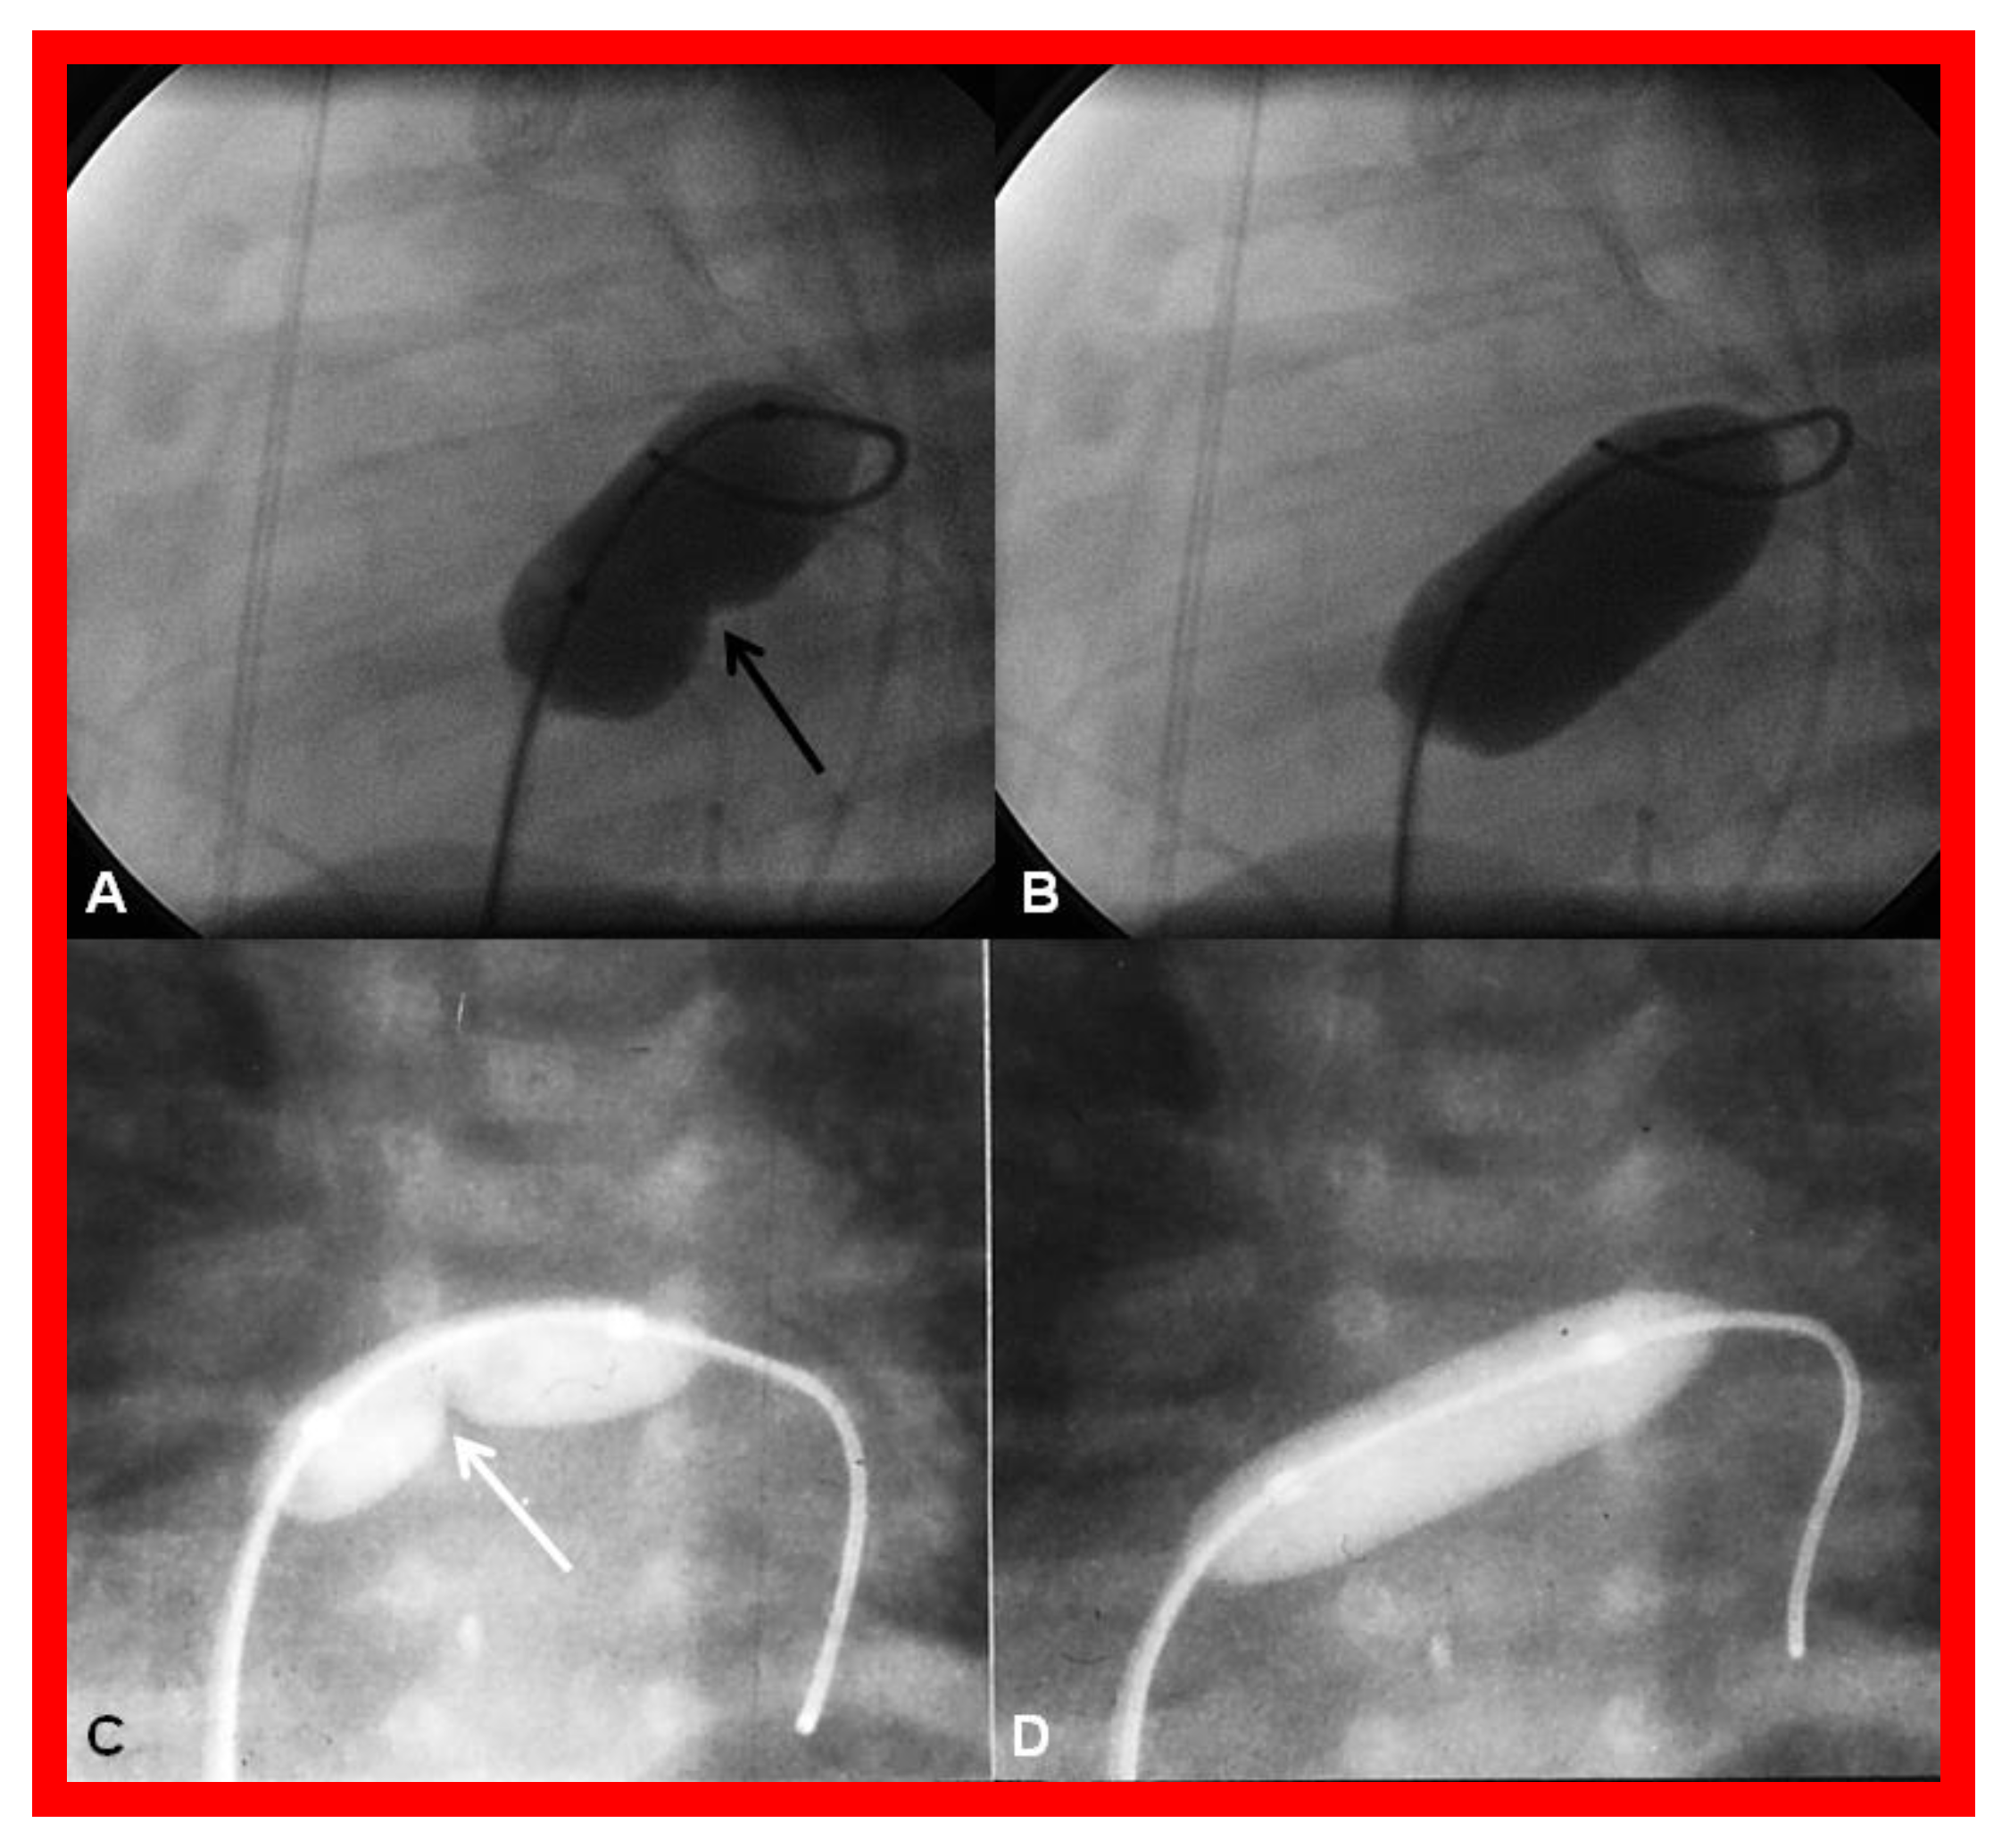

- Rashkind, W.J.; Miller, W.W. Creation of an atrial septal defect without thoracotomy. J. Am. Med. Assoc. 1966, 196, 991–992. [Google Scholar] [CrossRef]

- Park, S.C.; Neches, W.H.; Zuberbuhler, J.R.; Lenox, C.C.; Mathews, R.A.; Fricker, F.J.; Zoltun, R.A. Clinical use of blade septostomy. Circulation 1978, 58, 600–606. [Google Scholar] [CrossRef]

- Shrivatsava, S.; Radhakrishnan, S.; Dev, V.; Singh, L.S.; Rajani, M. Balloon dilatation of atrial septum in complete transposition of great arteries—A new technique. Indian Heart J. 1987, 39, 298–300. [Google Scholar]

- Rao, P.S. Static balloon dilation of atrial septum (Editorial). Am. Heart. J. 1993, 125, 1826–1827. [Google Scholar]

- Gewillig, D.; Boshoff, L.; Mertens, L. Creation with a stent of an unrestrictive lasting atrial communication. Cardiol. Young 2002, 12, 404–407. [Google Scholar] [CrossRef] [PubMed]

- Eicken, A.; Gildein, H.P.; Schreiber, C.; Balling, G.; Hess, J. Stenting of a restrictive foramen ovale in a patient with hypoplastic left heart syndrome. Intern. J. Cardiol. 2006, 113, 254–256. [Google Scholar] [CrossRef] [PubMed]